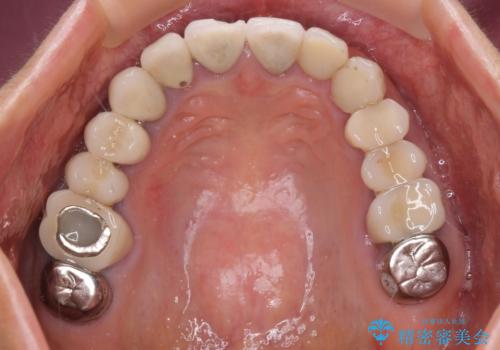

- 以前治療した歯が欠けたり、痛みを感じたりしているとのことで来院された患者様です。

アメリカ国内を転々としながら治療を行ったため治療跡がモザイク様で、クラウンが壊れていたり、抜歯が必要であったりしていました。

上下左右すべての奥歯に処置が必要であり、同時に行うと食事が取りにくくなってしまったり、手前の歯に負担がかかって初診時よりも状況が悪化したりする可能性があるため、片方ずつ処置を進めて行くこととしました。

下顎右側は骨造成を併用してインプラント治療を行い、その他の奥歯もインプラントや歯周外科処置を併用して補綴治療を進め、最後に前歯部の欠けてしまったセラミッククラウンを作り替えることとしました。